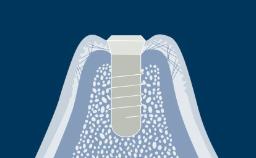

This module will define risk factors, both systemic and local, in relation to implant therapy as well as relative and absolute contraindications to implant placement.

- identify the local risk factors associated with implant therapy